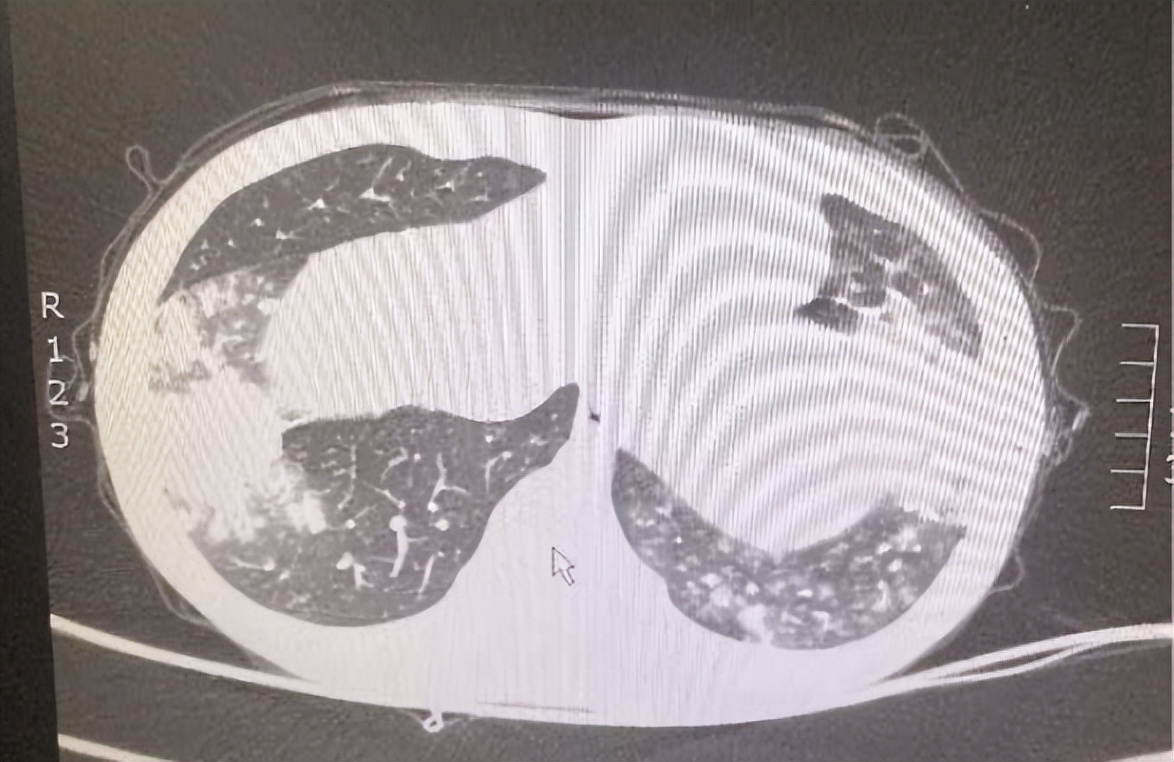

7岁男童,因“发热、咳嗽5天”入院。院前以高热为主,已予治疗,患儿体温无好转,查肺部CT示双肺炎症。急需完善支气管镜肺泡灌洗术,并送检病原学明确病因。

反复或持续的高热,咳嗽或不伴有咳嗽,肺部CT都显示出部分肺叶实变,这种波及各年龄段的大叶性肺炎,已引起我科门诊及住院部医生的特别注意。